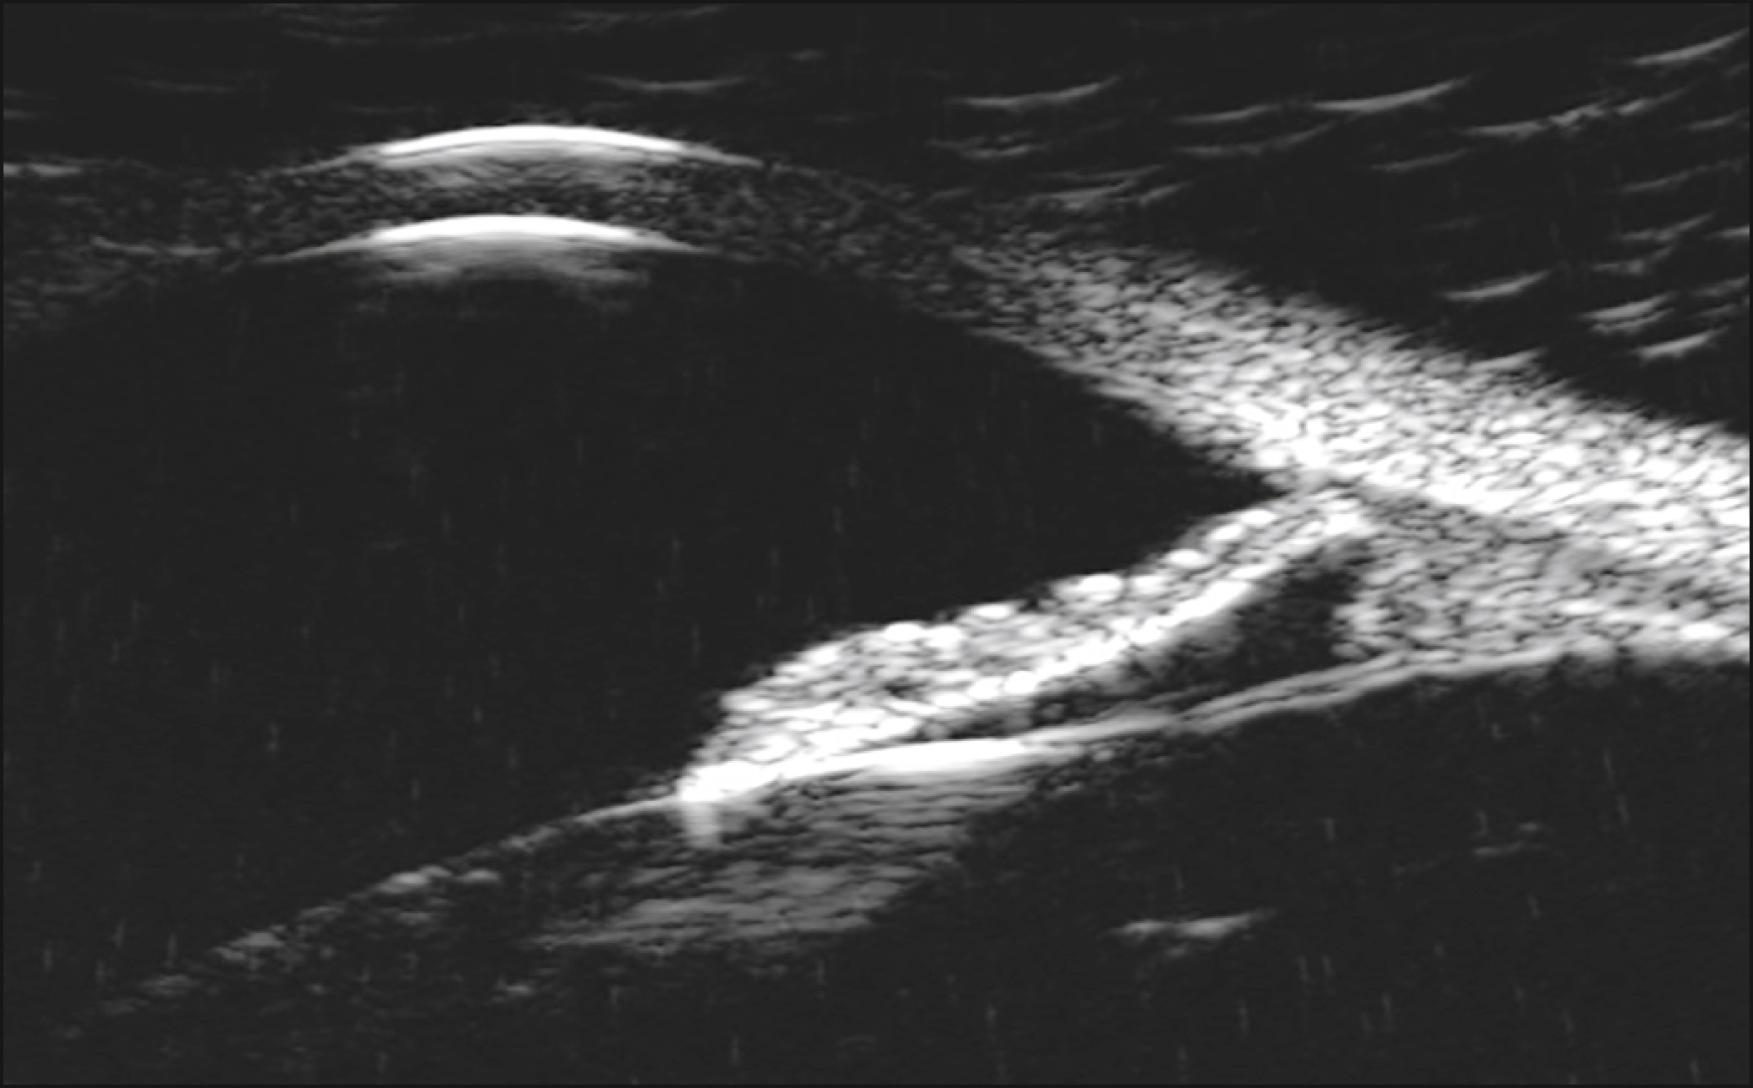

An axial scan (vertical and horizontal—marker on probe should be nasal for horizontal scan and up [12:00] for vertical scan) is first obtained to get an overall view of the AC and to assess the AC depth, lens thickness, and structure, which can be an important part of surgical planning ( Fig. 16.5 ). Next, longitudinal views are critical for evaluating angles, ciliary body, sulcus, and zonules. The probe marker should be directed toward the pupil or the clock hour. It is important to be consistent and label all scans, such as L1:30, so that when referring to the images, the location will be clear ( Fig. 16.6 ). The best image is always acquired when the sound beams are perpendicular to the ocular structures being examined. When perpendicular to the cornea, one can see the highly reflective epithelial and endothelial surfaces.

Fig. 16.6, Longitudinal scan through angle.